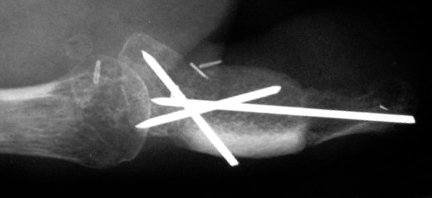

Late Xray, showing the intercalated iliac crest graft between the recipient proximal phalanx and the donor distal phalanx. The inclusion of the tip of the distal phalanx prevents late distal resorption, which occurs when the distal phalanx is not included.